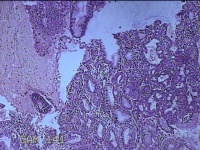

子宫腔内膜组织

性别

女

年龄

44岁

临床诊断

子宫异常出血、甲亢、轻度贫血

一般病史

阴道流血20天,加重1天。

标本名称

大体所见

灰白暗红色不规则碎组织3x2.8x0.3cm一堆。

图3

貌似增生反应子宫内膜。